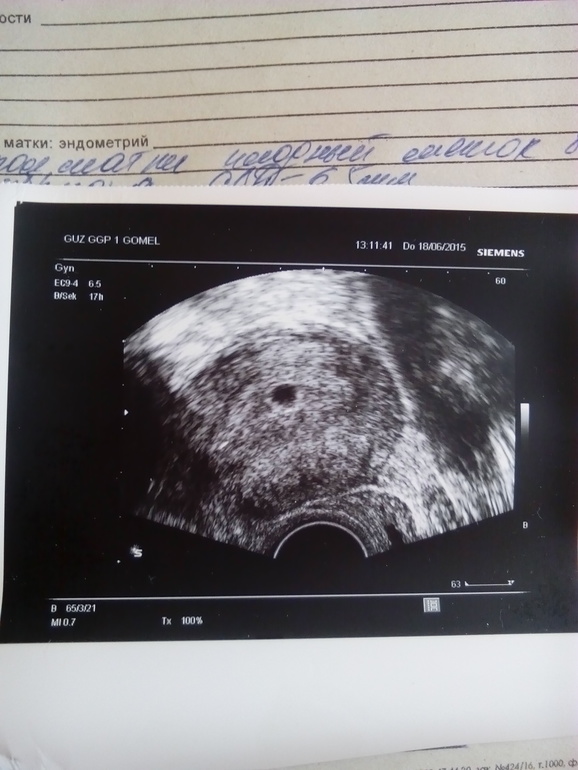

сегодня сходила на УЗИ,поставили 3-4 недели, ПЯ в матке)))))но эмбриончика сказали еще нет,рано!!!!Смотрю на снимок и мне интересно,что эта за белая чёрточка в ПЯ????Может это и зарождается эмбриончик????а????посмотрите девчат)))))на УЗИ через 10 дней!!!

Мне вот интересен отросточек в черном пятнышке)))что это интересно???

У меня на узи была такая же чёрточка,врач говорила-стволовые клеточки из которых образовывается эмбриончик!)

Ааа,а то смотрю что четкая чёрточка в ПЯ))))вот и голову себе ломаю что же это,если еще эмбриончика пока не видно )))